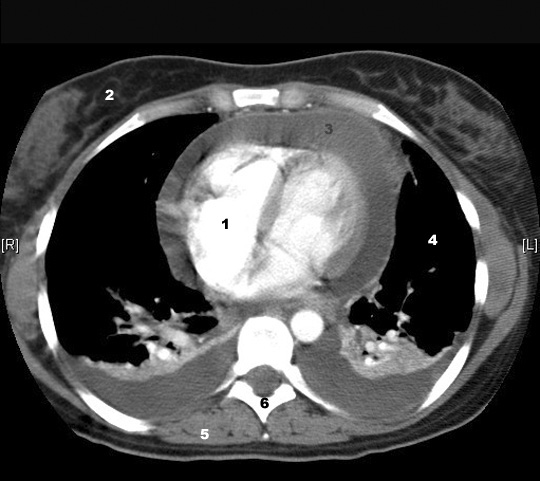

Identify the densities in the CT. Click the image for labeling.